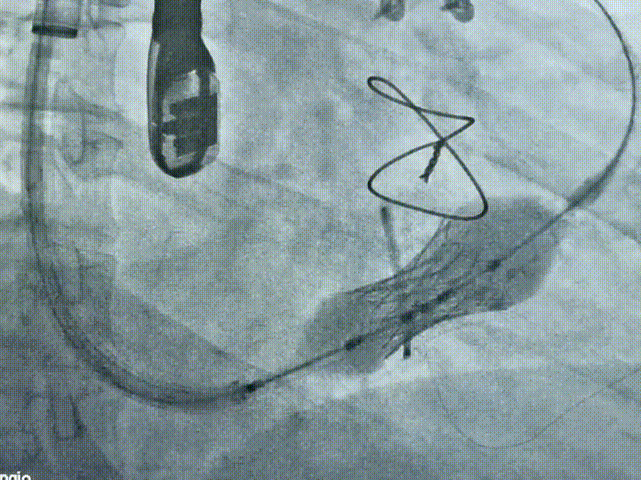

手术在复合手术室内进行,患者全麻后经右侧颈静脉穿刺插入导丝和鞘管建立输送轨道,导丝远端进入右肺动脉。将压握好介入瓣膜的输送系统沿导丝推送至三尖瓣瓣环位置,借助瓣膜显影和输送系统的三个显影点,实现瓣膜的精准定位,因右心系统低压力,无需快速起搏直接充盈球囊实现瓣膜释放。

术中释放过程

术后造影